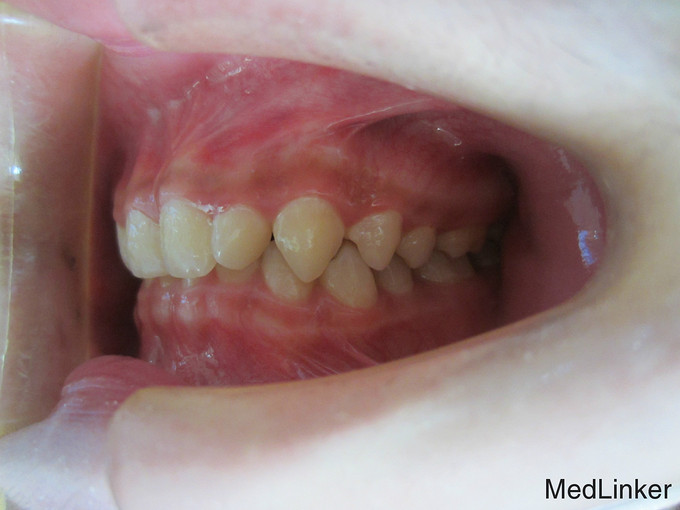

检 查:双侧颞下颌关节开口弹响,开口度一度; 模型测量分析:3度深覆合,上下颌轻度拥挤,spee曲线陡峭,上下颌尖牙尖锐、宽度较小,; 头 颅 侧位片:下颌平面角低角,下颌后缩,余正常; 辅 查:曲面断层片、头颅侧位片,双侧颞下颌关节片

诊断:深覆合、下颌后缩导致颞下颌关节负担加重,引起关节紊乱 治疗:一期:制作合平面导板,戴用一月后关节症状减轻,确定病因; 二期:带用固定矫治器,首先排齐上颌4个月,之后配合平面导板及摇椅弓排齐整平下颌5个月,调整上下颌咬合关系3个月,精细调整2个月,保 持1个月后拆除矫治器,患者自觉关节症状明显好转,制作保持器保持。